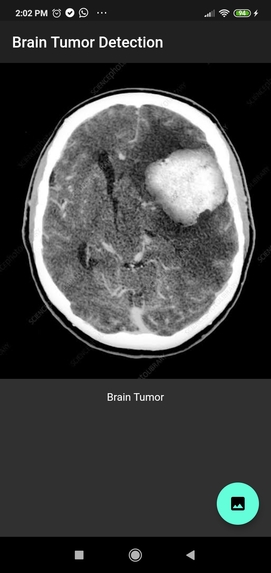

Android App with a machine learning approach to detect whether an MRI image of a brain contains a tumor or not.

The App working fine and handle all kind of image resolution